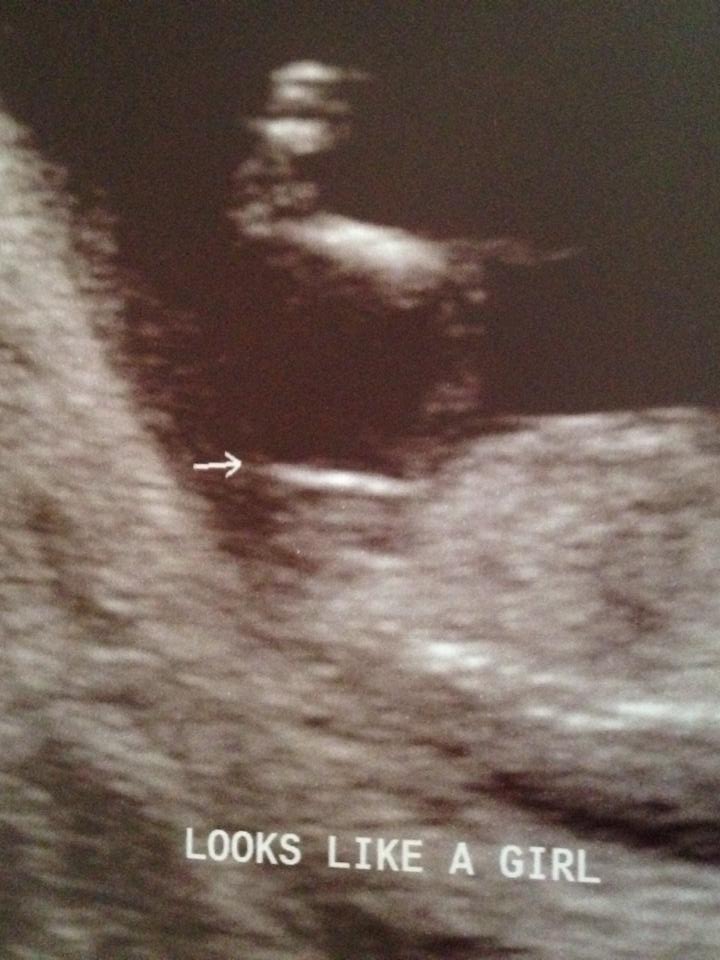

This is my ultrasound pic from my nt scan.. wondering what ya'll see :) Attachment 21100

looks like a girl nub but how far along are you

that was my 13 week Nt scan. Im 15 now

I'd say girl too

Girly

Def girl!